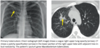

What is a radiographic sign for empyema? A similar finding can be seen in what entities (diagram)?

- Empyema is infection within the pleural space.

- There are three stages in the development of an empyema:

- Free-flowing exudative effusion: Can be treated with needle aspiration or simple drain.

- Development of fibrous strands: Requires large-bore chest tube and fibrinolytic therapy.

- The fluid becomes solid and jelly-like: Usually requires surgery.

- Although pneumonia is often associated with a parapneumonic effusion, most pleural effusions associated with pneumonia are not empyema but are instead a sterile effusion caused by increased capillary permeability.

- An empyema conforms to the shape of the pleural space, causing a longer air-fuidlevel on the lateral radiograph. This is in contrast to an abscess, which typically is spherical and has the same dimensions on the frontal and lateral radiographs.

- The split pleura sign describes enhancing parietal and visceral pleura of an empyema seen on a contrast-enhanced study.